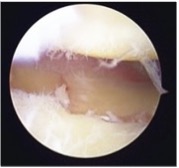

橈骨遠位端骨折に対する鏡視併用手術

橈骨遠位端骨折は頻度の高い骨折の一つで、特に関節内骨折については関節鏡を併用し従来のX線のみでは整復が不十分な関節面の整復を行っています。

鏡視下整復前

整復後